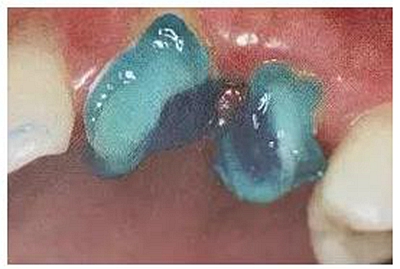

4. 根管潮濕度的控制

專家及業(yè)內學者提出的濕粘接的概念,臨床上由于口腔的復雜和根管的特殊性,濕粘接技術的控制很有難度。既不過分干燥又不過分潮濕,根管壁表面濕度均勻。

選用大錐度牙膠尖無疑能達到很好的效果。

(剪去吸潮紙尖尖部)

(圓形根管的干燥)

(扁圓形根管的干燥)

操作時:剪去紙尖尖部,插入根管,稍微加以壓力,上下小幅度貼根管壁四周提拉,均勻吸收水分。當扁圓形根管時可使用兩根大錐度牙膠尖。